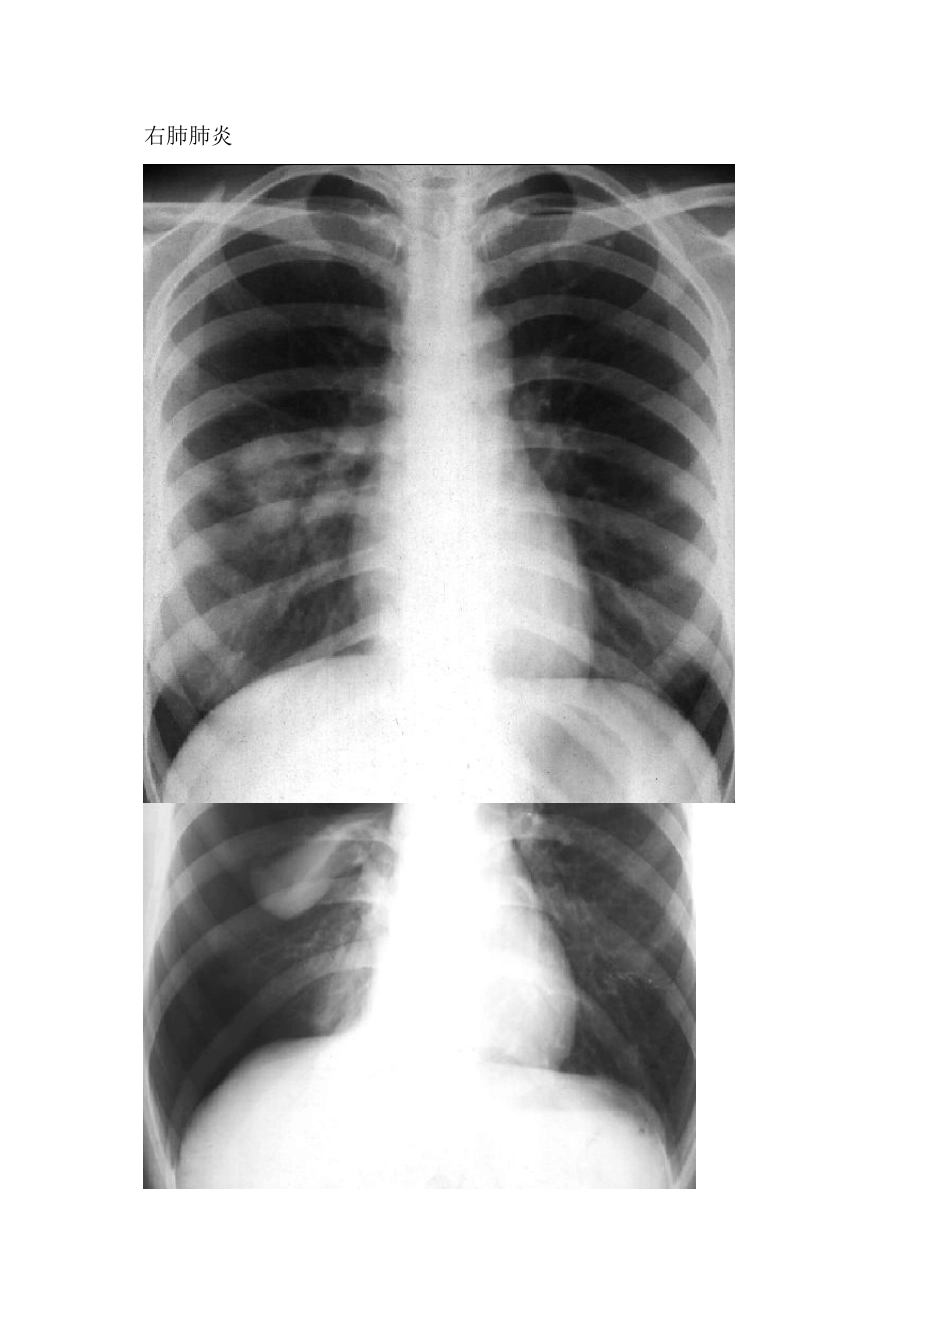

心包大量积液-烧瓶心 二尖瓣狭窄-梨型心 心高血压性心脏病-靴型心 左下大叶性肺炎实变期 右肺肺炎 右肺气胸 左侧液气胸 右侧中量胸腔积液 右侧大量胸腔积液 肺转移癌 小肠单纯型梗阻 股骨颈骨折 胫骨、腓骨骨折 左肺癌 胃溃疡 胃肠穿孔 肠梗阻 正常上肢骨